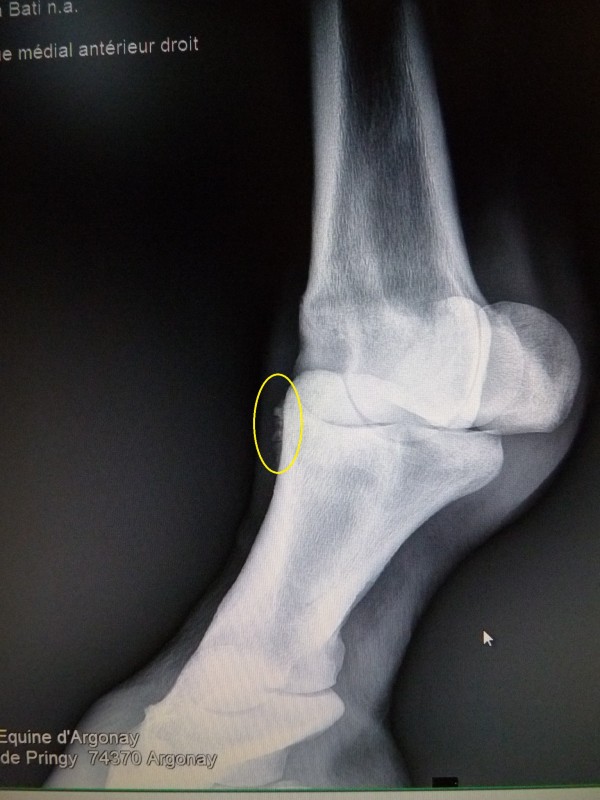

j'espère que ce ne sera pas trop grave, tu le vois quand le veto ?